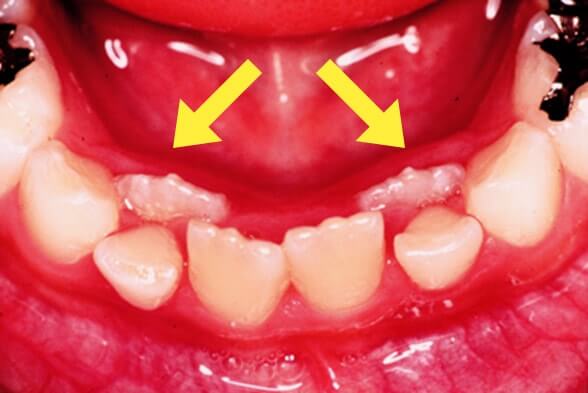

萌出異常(乳歯の裏から歯が生えてきた)